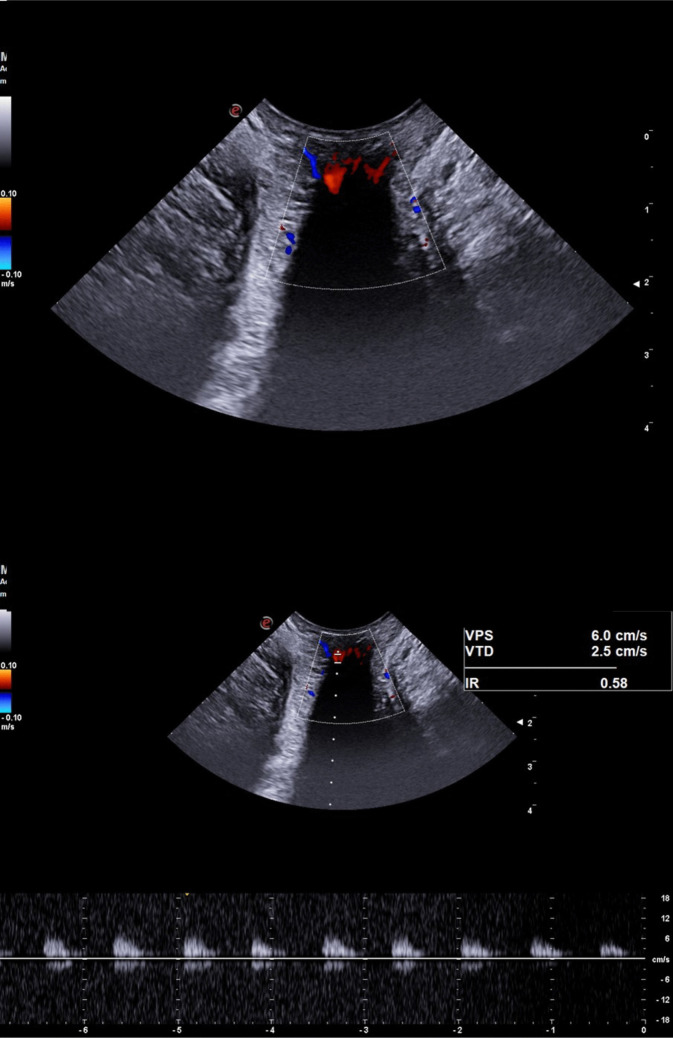

Methods: A prospective observational study was conducted on 50 healthy controls (HC) and 94 HD patients classified by Goligher grade. All underwent TPUS with Doppler assessment to record vascular patterns and quantify peak systolic velocity (PSV), end-diastolic velocity (EDV), and resistance index (RI).

Results: A vascular Doppler pattern was observed in 92.6% of HD patients vs. 50% of HCs (p < 0.001). HD patients showed significantly higher PSV (11.1 ± 3.6 cm/s vs. 8.3 ± 2.9 cm/s, p < 0.001) and RI (0.8 ± 0.1 vs. 0.7 ± 0.1, p = 0.015), with no significant difference in EDV. Among Goligher groups, grades III and IV showed significantly elevated PSV compared to HCs. No differences were observed in EDV or RI among subgroups.